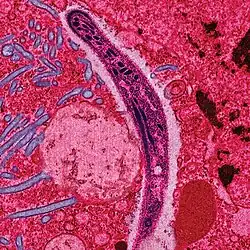

- A disease that emerges within a population that is new or the number of infectious cases within a population or geographic area rapidly increases. Since 1940 over 300 new infectious diseases have been discovered, some of the most well known being severe acute respiratory syndrome (SARS), methicillin-resistant staph (MRSA), and Human Immunodeficiency Virus (HIV). Many drug-resistant strains of diseases are becoming more common and 71% of these new infectious diseases start in the wildlife. As globalization increases, infectious diseases will continue to affect a larger and wider population. [4] Classification of disease is as follows; an epidemic is a local outbreak of a rare disease. When this disease spreads through many human populations across a large region, it is then classified as a pandemic.